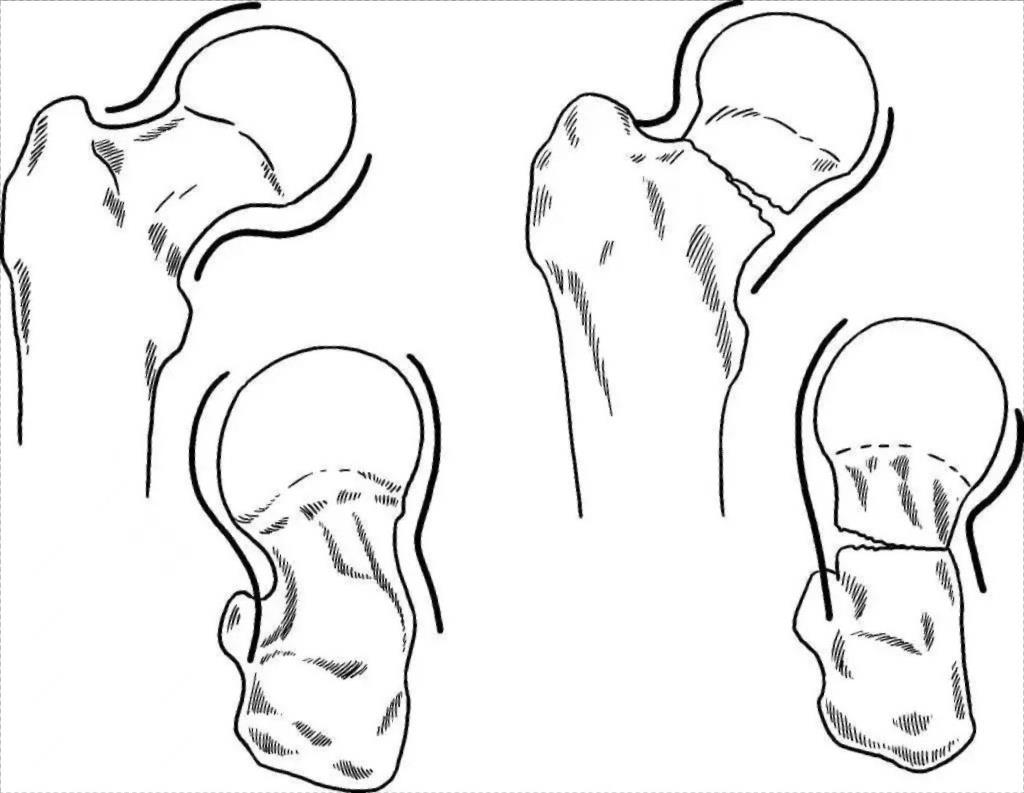

Если репозиция не достигается вышеуказанными методами, это обычно указывает либо на перелом головки бедренной кости, либо на ротационное разделение между головкой и шейкой (рис. 1А), либо на вставку где-то между головкой и шейкой. шея.(Это может произойти в любом из типов Garden II, III или IV).В этом случае ротация пораженной конечности для совмещения перелома головы и шейки уже неэффективна.Чтобы избежать разреза и репозиции, для репозиции перелома можно использовать технику чрескожного введения иглы.

Метод закрытой репозиции, описанный выше, позволяет добиться необходимой репозиции примерно в 98% случаев переломов шейки бедра.Чем лучше совмещение перелома, закрытого или надрезанного, тем лучше прогноз.Обычно степень переломо-вывиха, показанная на рентгенограмме, меньше, чем реальная степень переломо-вывиха.Поскольку совмещение перелома напрямую влияет на заживление перелома и возможность некроза головки бедренной кости, необходимо правильно оценить рентгенограмму после совмещения перелома.Если S-образная кривая не является плавной или прерывистой, это свидетельствует о том, что перелом шейки бедренной кости не достиг анатомической репозиции (рис. 2).

Рис. 1. Перелом шейки бедренной кости, вправленный с помощью чрескожной иглы.

Рис. 2. Рентгенограммы перелома шейки бедренной кости с непрерывной внешней кривой в анатомическом положении и прерывистой внешней кривой в неанатомическом положении.